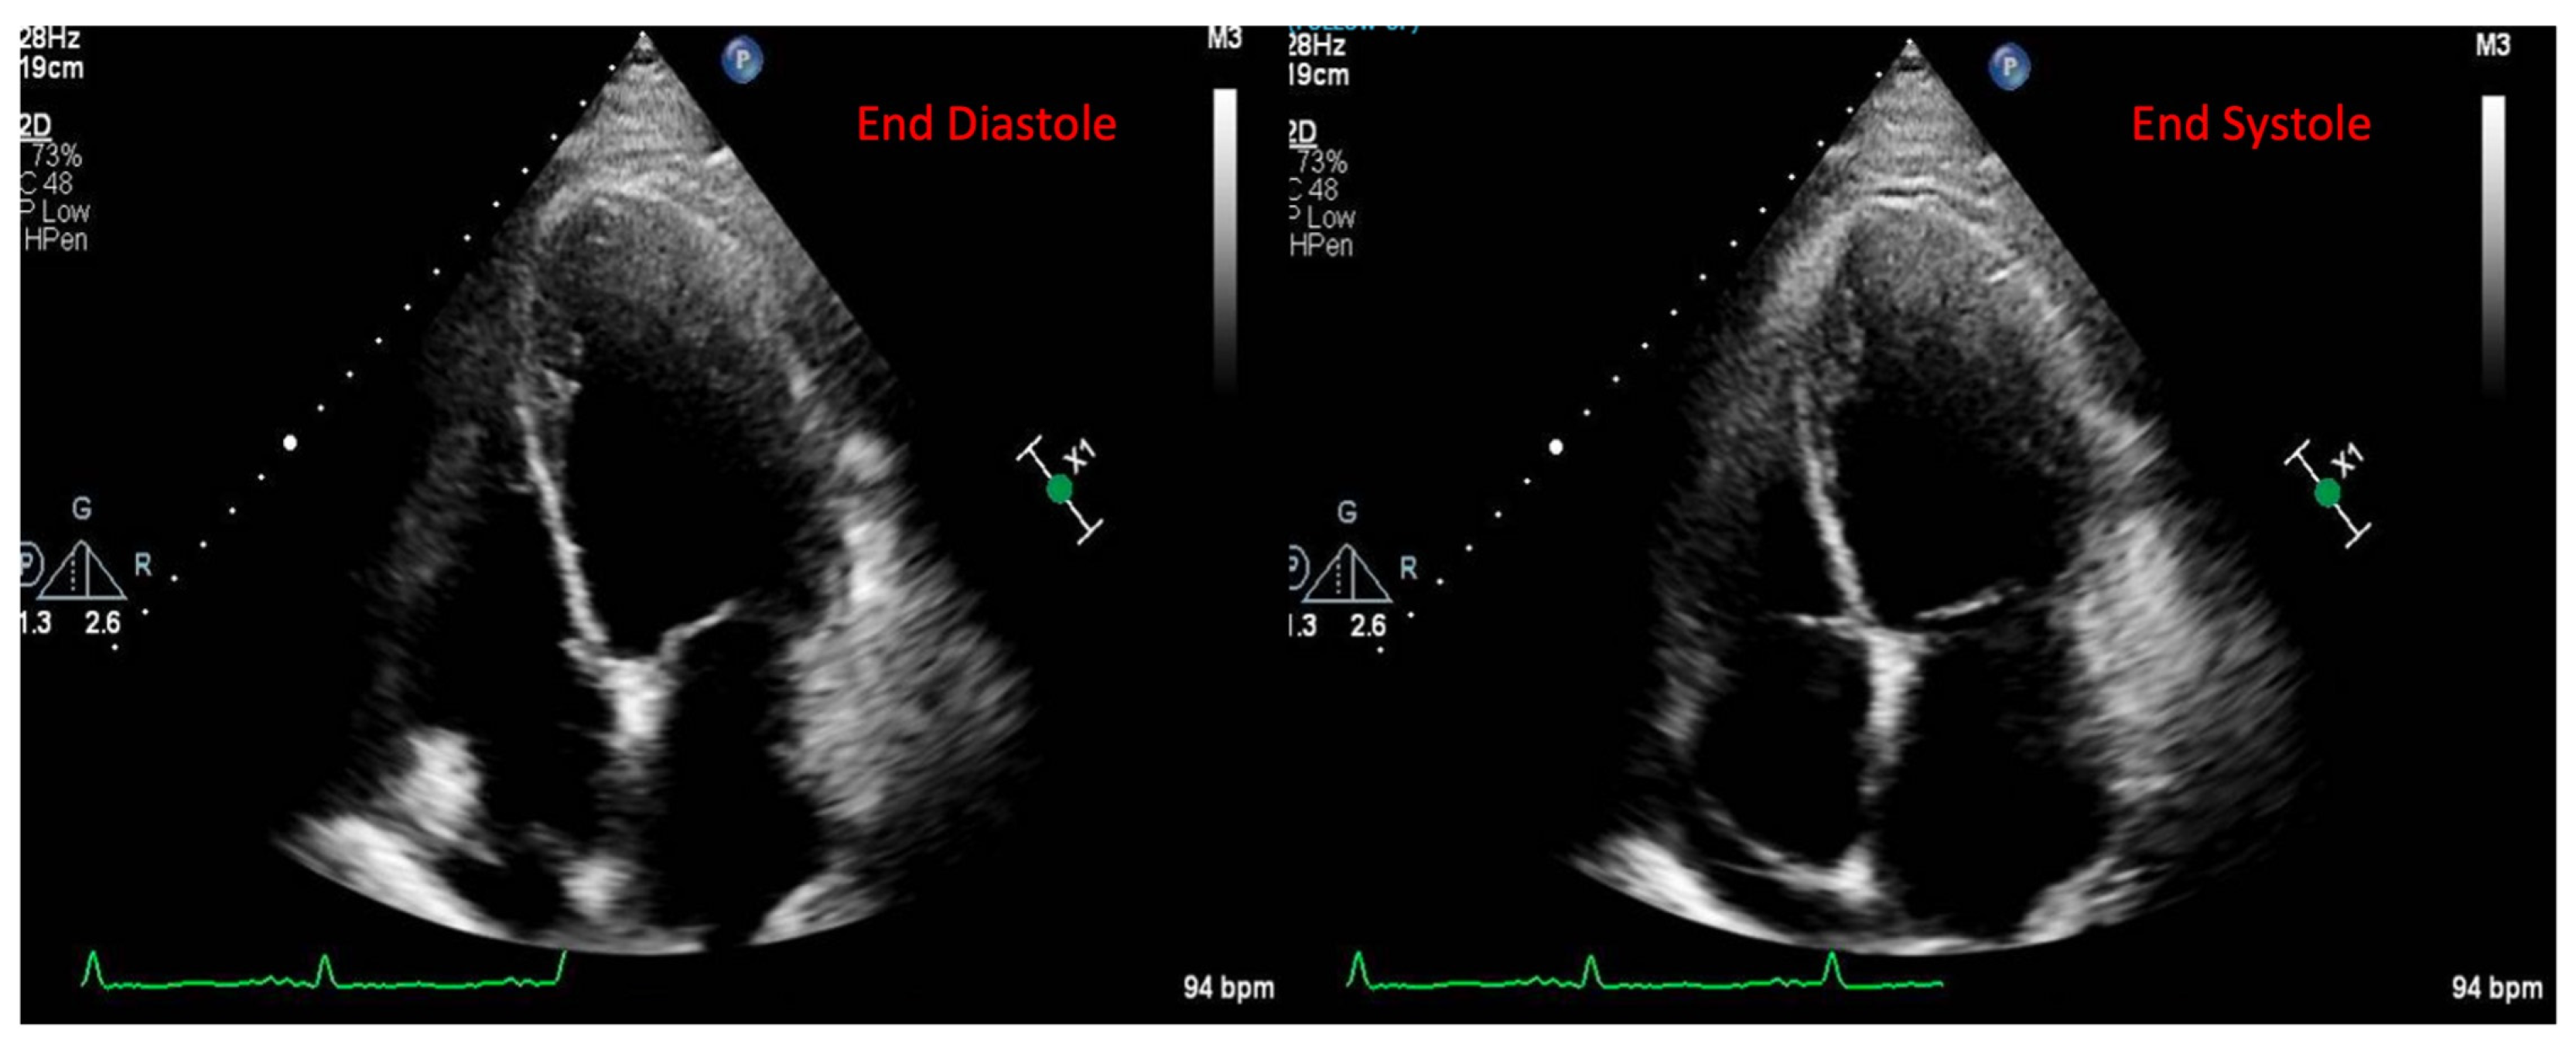

2.1. Echocardiography

- Awadalla, M.; Mahmood, S.; Groarke, J.; Liu, S.; Hassan, M.Z.O.; Murphy, S.P.T.; Jones-O’Connor, M.; Nohria, A.; Heinzerling, L.M.; Sullivan, R.J.; et al. Decreased global longitudinal strain with myocarditis from immune checkpoint inhibitors and occurrence of major adverse cardiac events. J. Am. Coll. Cardiol. 2019, 73, 1532. [Google Scholar] [CrossRef]

- Tamura, Y.; Tamura, Y.; Takemura, R.; Yamada, K.; Taniguchi, H.; Iwasawa, J.; Yada, H.; Kawamura, A. Longitudinal Strain and Troponin I Elevation in Patients Undergoing Immune Checkpoint Inhibitor Therapy. JACC CardioOncol. 2022, 4, 673–685. [Google Scholar] [CrossRef]

- Quinaglia, T.; Gongora, C.; Awadalla, M.; Hassan, M.Z.O.; Zafar, A.; Drobni, Z.D.; Mahmood, S.S.; Zhang, L.; Coelho-Filho, O.R.; Suero-Abreu, G.A.; et al. Global Circumferential and Radial Strain Among Patients With Immune Checkpoint Inhibitor Myocarditis. JACC. Cardiovasc. Imaging 2022, 15, 1883–1896. [Google Scholar] [CrossRef]